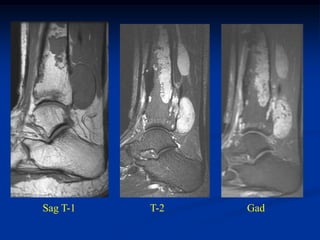

CLASSIC Case #123

12 year female with chondroblastoma proximal tibia

Coronal post gad MRI

Sagittal T-2 MRI